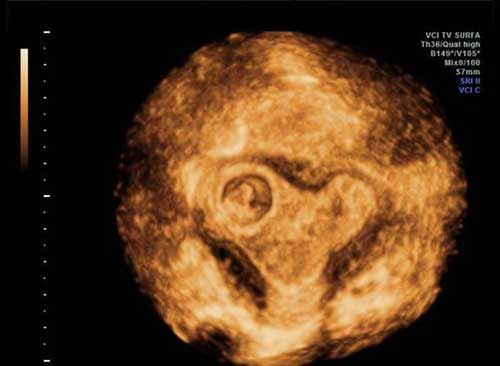

Challenge your diagnostic skills: What's your diagnosis based on these images from a 14-week fetus?